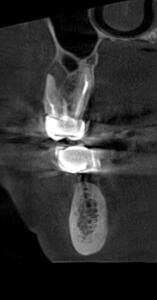

Клинические случаи в эндодонтии